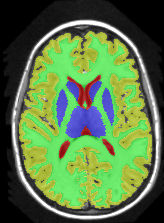

| ground truth | a-exp [7, 8] | QPBO [25, 8] | ours | |

In this application our method outperformed QPBO in most cases and a-exp in all cases. In fact a-exp always converged to a weak local minima in this setting, see Fig. 15. Based on our experience the quality of a-exp result depends on various factors, e.g. tree complexity, the number of min-margins introduced, the order in which labels are expanded, and the initial solution. For the subjects that QPBO was able to find the global optimal Path-Moves either found the global optimal or a very close solution.

Figure 16 shows the results for Subject 1 with (and without) min-margins and Hedgehog prior. The third row shows the results when not using min-margins. Path-Moves converged after two iterations to a lower energy than a-exp, which converged after six iterations. In this case a-exp local minimum was due to the Hedgehog prior, see last row.

Table 1 compares the precision, recall and F1 score for each region individually, where . The higher F1 values correspond to better segmentation. In general, QPBO was unpredictable as in some cases it found the optimal solution and in other cases it left a large number of pixels unlabeled.

Table 2 show the results after dropping the hedgehog prior. In terms of Path-Moves, the mainly affected label after dropping the Hedgehog prior is the sub-cortical gray matter, as it started to grab parts of the gray matter, see Fig.16 second row, last column. Comparing Tables 1 and 2 it is clear that QPBO and a-exp benefited the most by introducing the hedgehog prior.